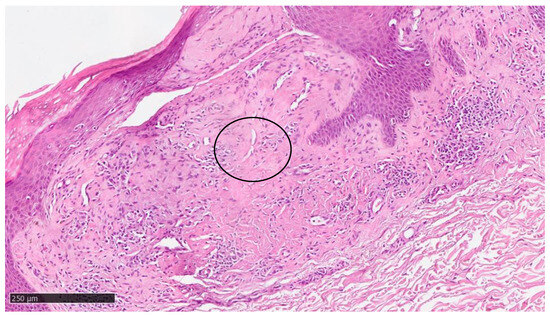

At our clinic, for a diagnosis of certainty regarding LA, an incisional biopsy was performed regarding the typical infiltrated plaques on the lower limbs. The histopathological investigations reported typical LA findings, such as the deposition of amyloid material at the papillary dermis, beneath the dermo-epidermal junction; there were also some areas with inconsistency regarding the melanic pigment and diffuse inflammatory infiltrate at the middle and superficial dermis. The epidermis was not interested in this infiltration and acts as an innocent bystander with acanthosis, hyperkeratosis, and elongation of the epidermal ridges (Figure 3, Figure 4 and Figure 5). With polarized microscopy, it was possible to appreciate the amyloid deposits beneath the dermo-epidermal junction (Figure 6).

Figure 4. Scanning magnification of the previous picture showing the amyloid deposition beneath the dermo-epidermal junction (black arrow) with the typical cleft (white spaces) and moderate lymphocytic infiltration in the middle dermis (hematoxylin–eosin; original magnification 10×).